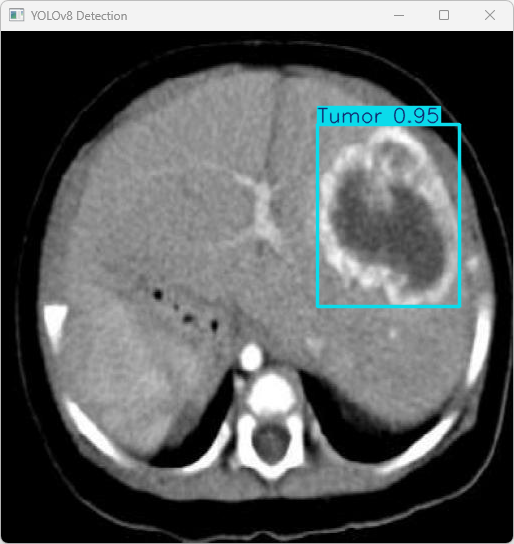

执行imgTest.py代码后,会将执行的结果直接标注在图片上,结果如下:

这段输出是基于YOLOv8模型对图片“imagetest.jpg”进行检测的结果,具体内容如下:

图像信息:

(1)处理的图像路径为:TestFiles/imagetest.jpg。

(2)图像尺寸为 512×512 像素。

检测结果:

(1)模型在该图片上检测到 1 个肿瘤(”1 Tumor”)

处理速度:

(1)预处理时间:4.8 毫秒

(2)推理时间:4.3 毫秒

(3)后处理时间:51.5 毫秒

模型在处理图片时非常高效,成功检测出 1 个肿瘤实例,并将结果保存到了指定目录。